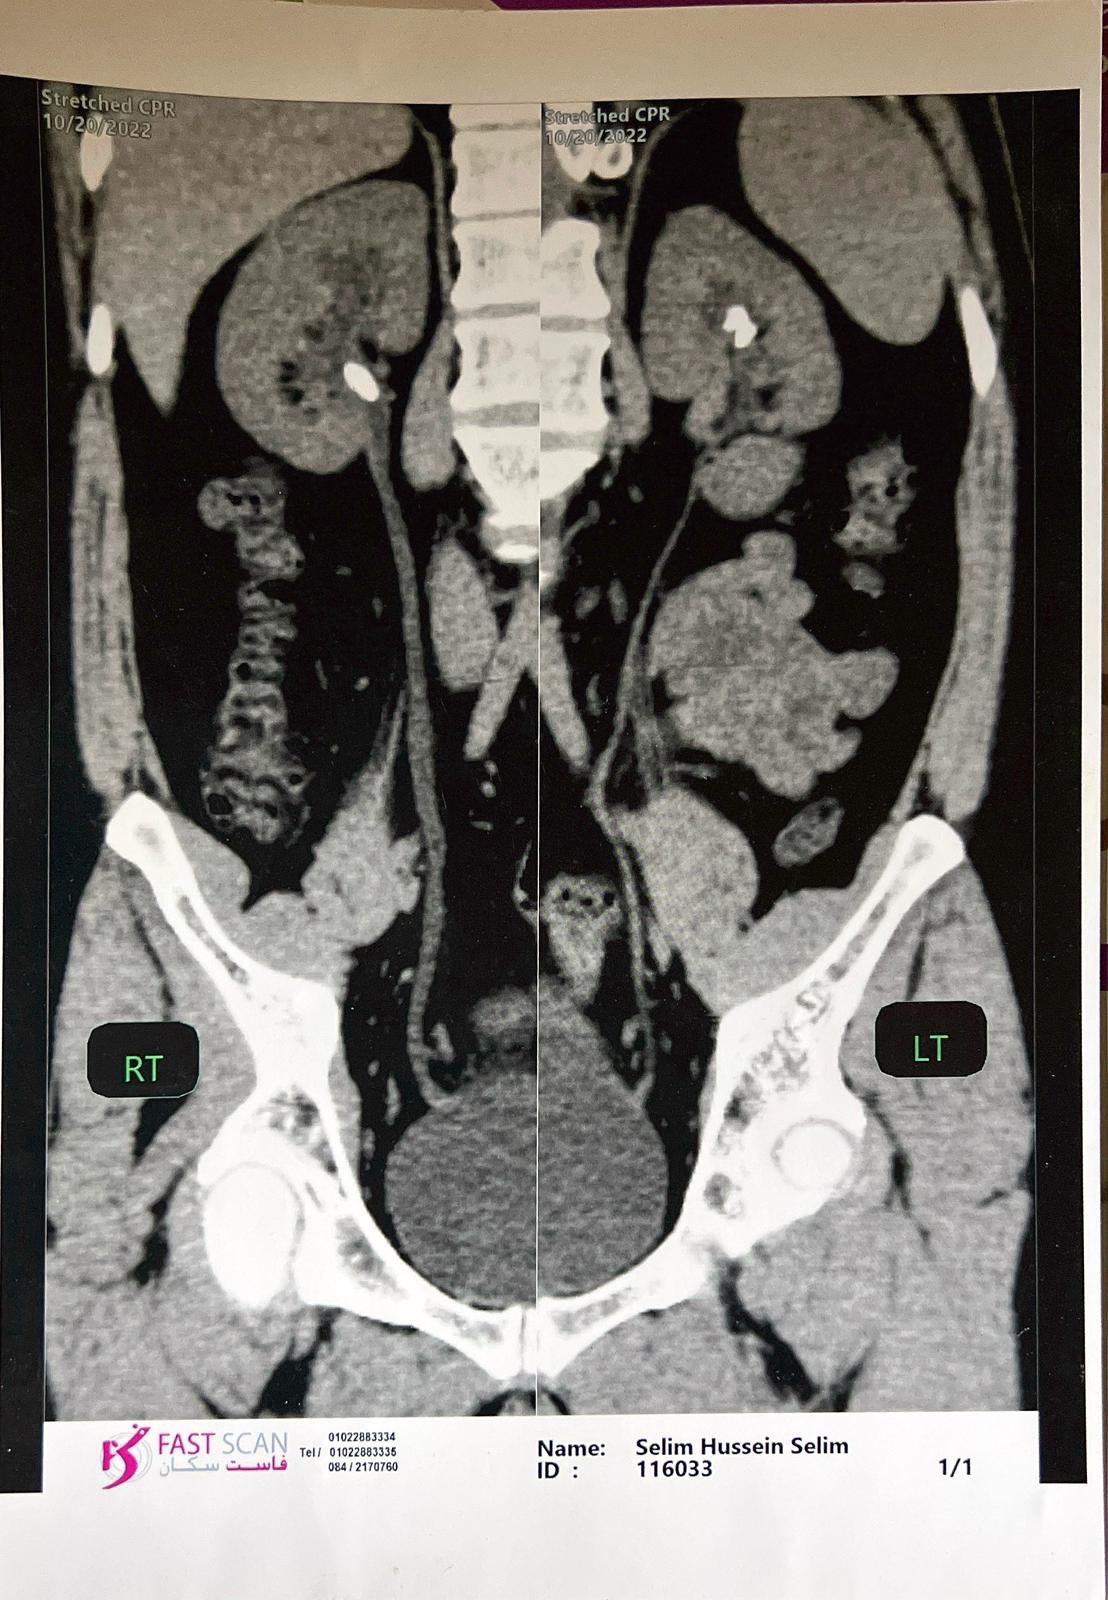

I am currently suffering from a severe kidney stone measuring four centimeters in length, a condition that is causing me excruciating pain on a daily basis. Due to the severely limited healthcare infrastructure in Gaza, there are no available facilities or specialists capable of performing the necessary surgical procedure to remove the stone.